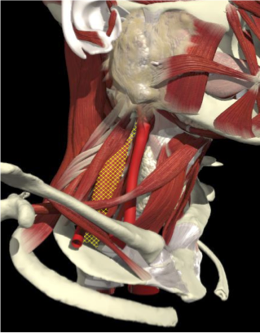

ACCURACY OF MUSCLE LOCALIZATION

- Muscles deep

- Not easily identified by surface landmarks

- Not palpable on examination

ACCURACY OF LOCALIZATION - SCALENES

ACCURACY OF LOCALIZATION LEVATOR SCAPULAE

LOCALIZATION OF MUSCLES IN DEEPER LAYERS

Layer 1

Layer 2

Layer 3

Splenius Capitis

Semispinalis Capitis

Longissimus Capitus

Semispinalis Cervicis

ACCURACY OF LOCALIZATION – DEEPER LAYERS

INJECTION SITES